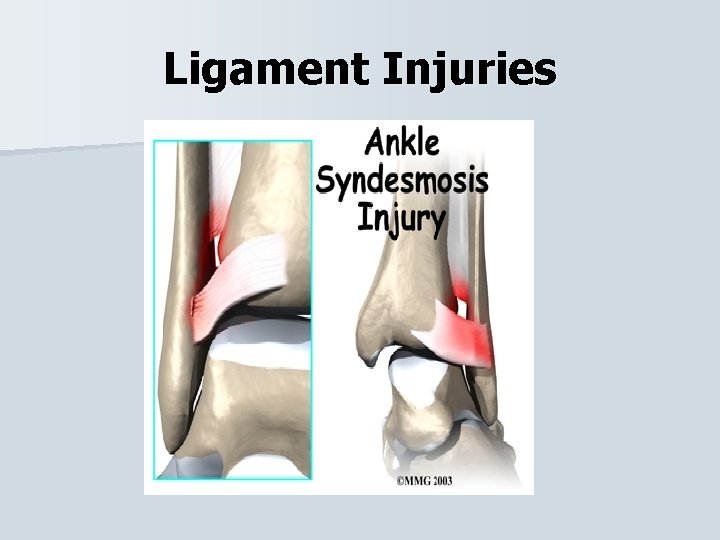

Ligament Injuries Syndesmosis – another type of ankle sprain that is a high ankle sprain injures the syndesmosis that binds the tibia and fibula together. When the ankle is either severely, everted or rotated, the talus can force the tibia and fibula to spread apart. Syndesmotic sprains take longer to heal.